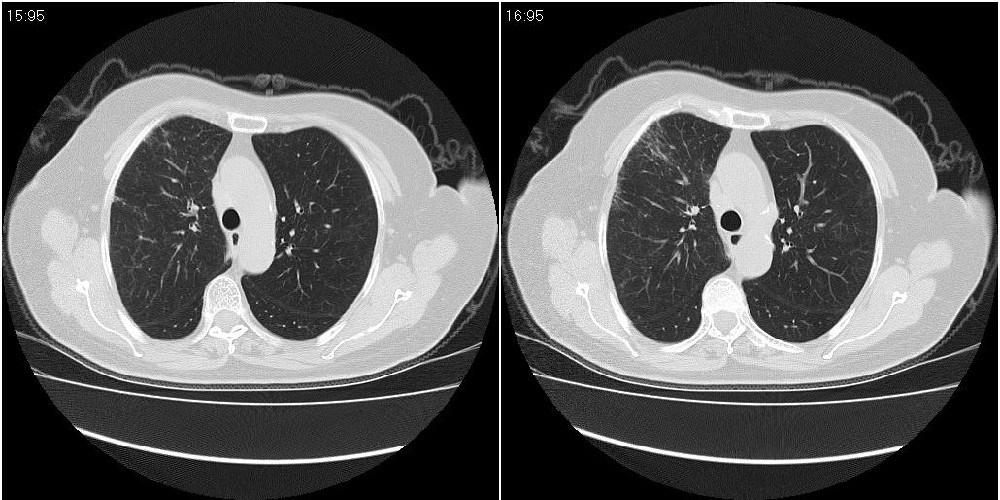

女性,72岁。去年9月份发现肺部病变,诊为肺结核并进行正规治疗至今,但复查后发现ct表现几乎没有变化。

右中间段支气管局限性狭窄,右中叶支气管亦稍显狭窄,但并未见明显占位表现,半年多了,无变化也许是好事,可能为炎性狭窄,建议继续随访。

双肺继发型tb并右中叶内膜tb,轻度支扩,左下胸膜肥厚粘连。

右中叶炎性改变,支气管狭窄但较光滑,占位可能性不大。

双肺继发性肺结核并右肺中叶节段性肺不张,左下胸膜肥厚粘连。

右肺中叶节段性肺不张,考虑结核或慢性炎症,建议做纤支镜检查。

双肺继发性肺结核并右肺中叶节段性肺不张